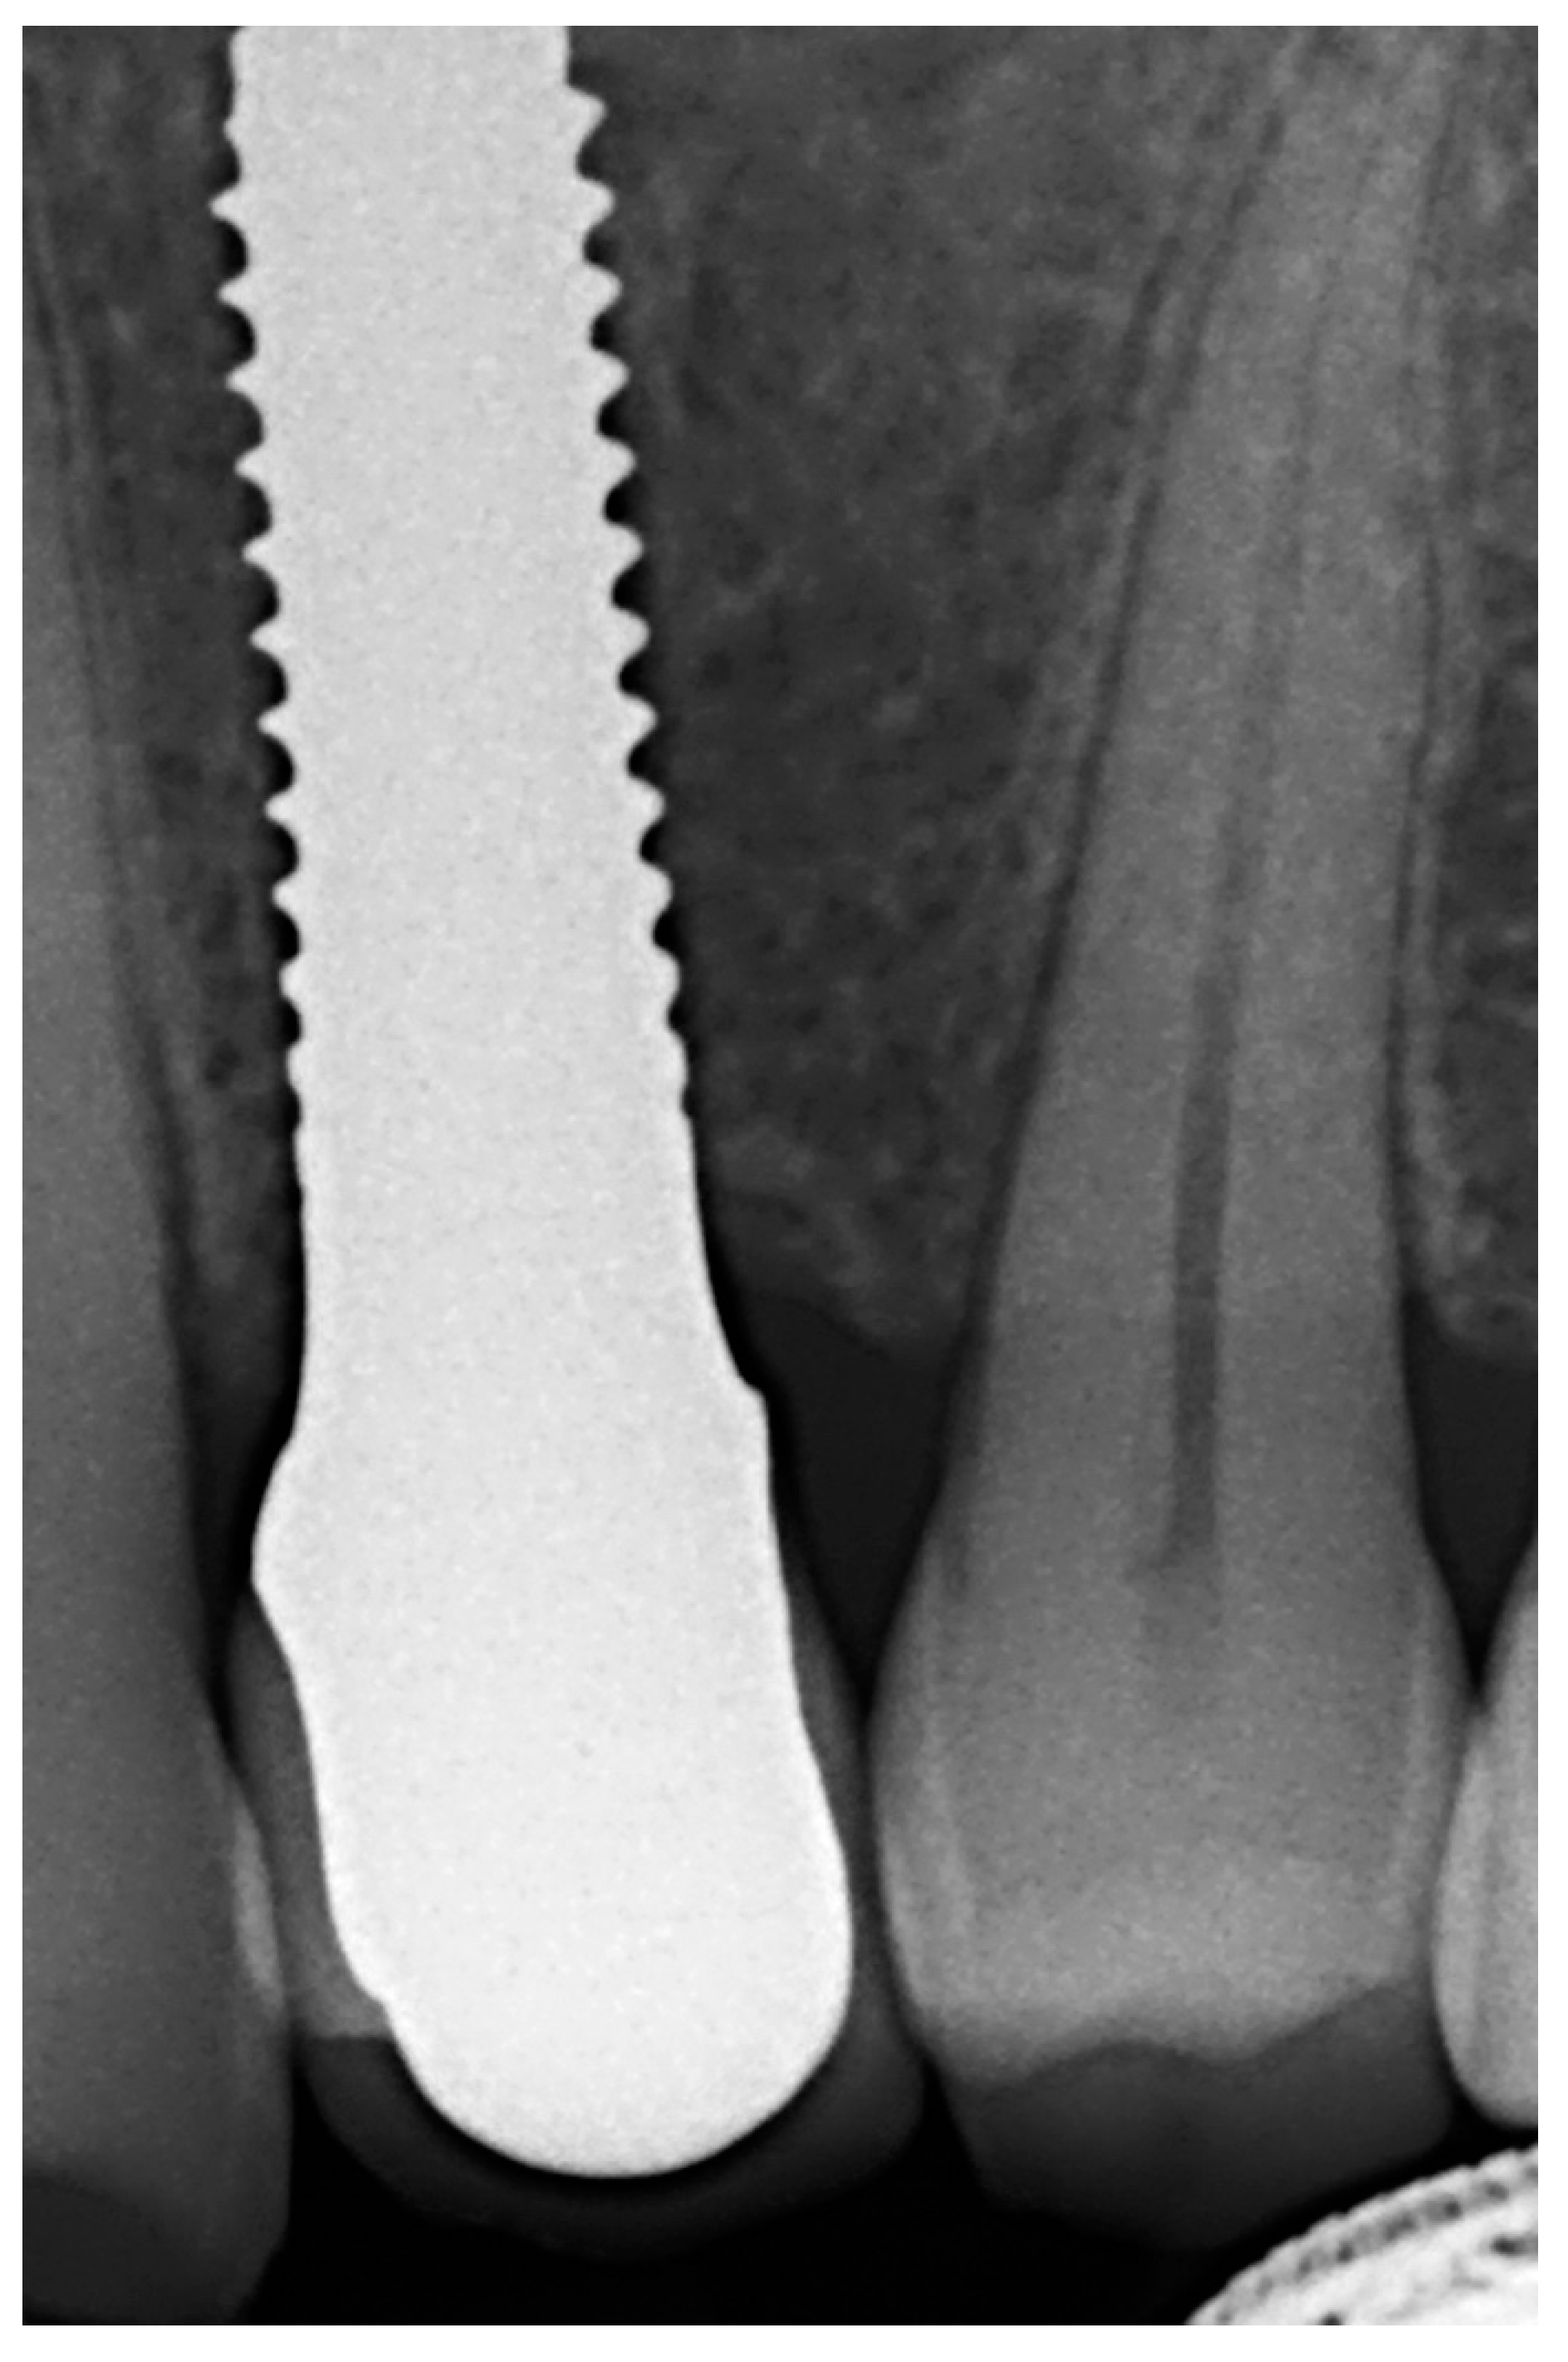

Afterwards, GBR procedures were performed if needed, a plastic abutment protector was placed, and flaps were closed with single sutures to ensure transmucosal implant healing. An intraoral radiograph was taken immediately after surgery (Figure 3). Postoperative medication was then prescribed in the form of amoxicillin 500 mg (or clindamycin 300 mg in patients allergic to penicillin) every 8 h for 7 days, ibuprofen 600 mg every 8 h for four days, and chlorhexidine rinses twice a day for 15 days.

Figure 3. Immediate postoperative intraoral X-ray view after one-piece zirconia implant placement.